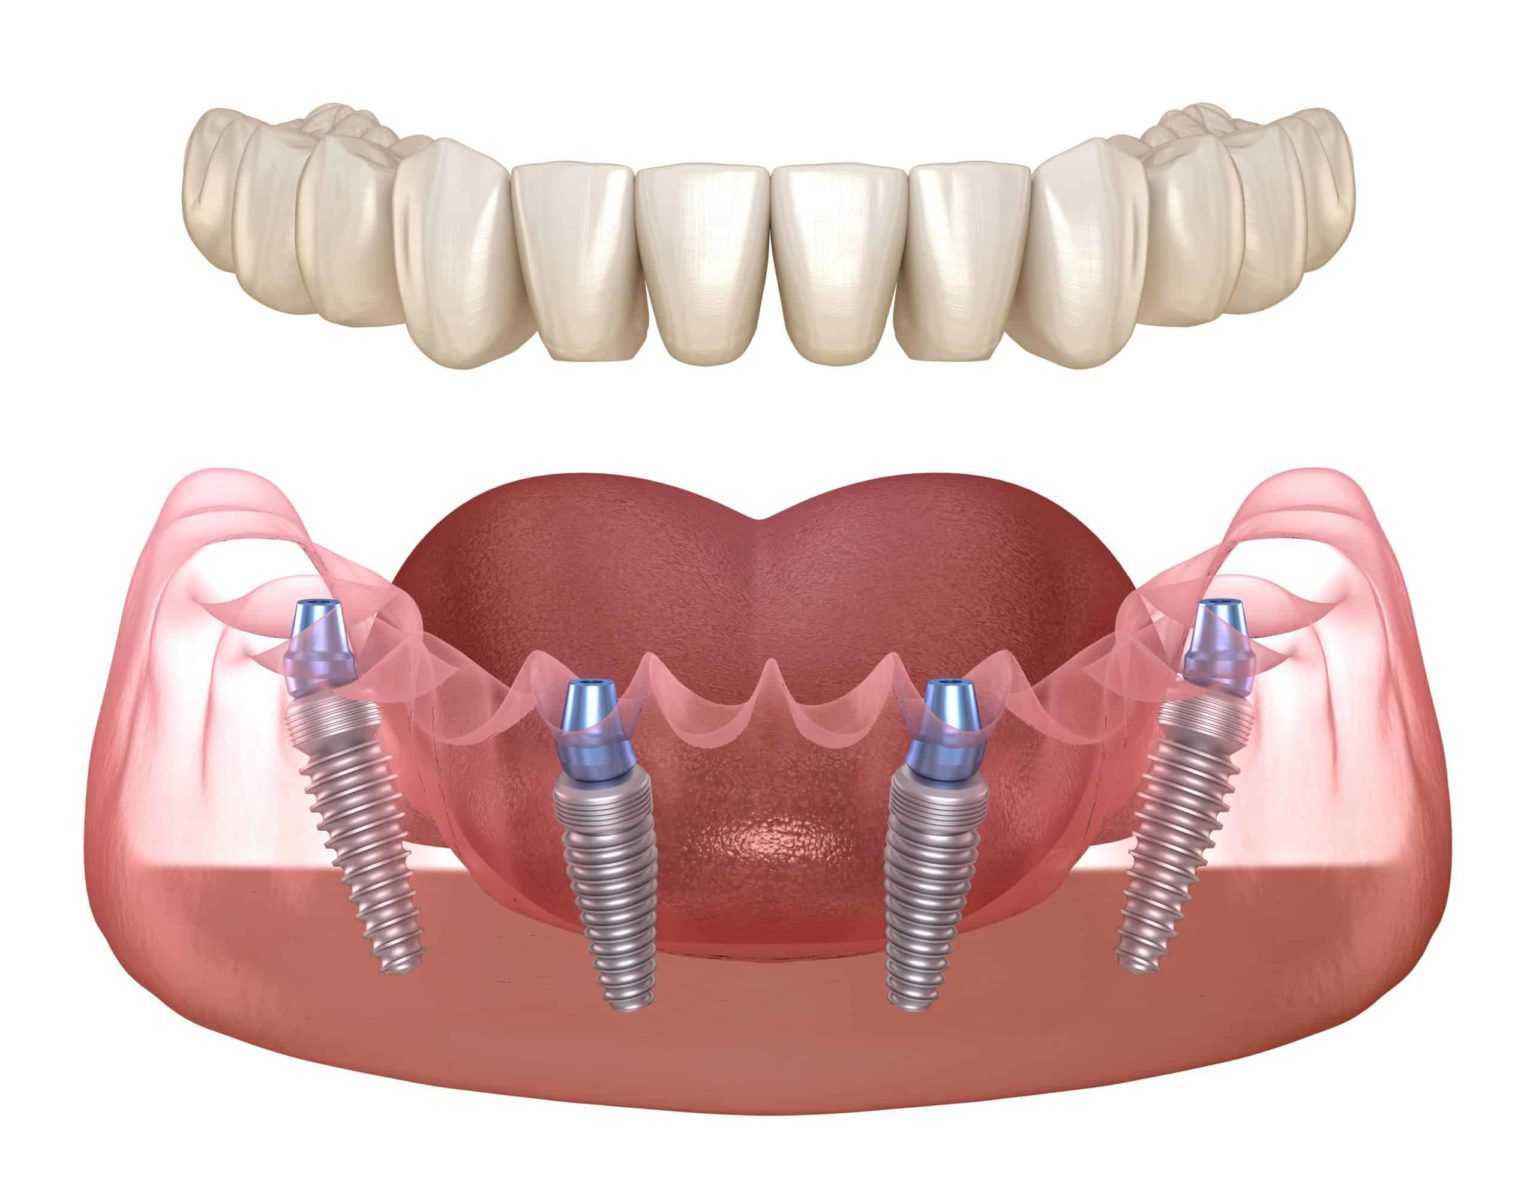

Методика базальной имплантации отвечает всем потребностям пациента и требованиям прогрессивной стоматологии! В отличии от распространенных, в настоящее время, методик ALL ON 4 и ALL ON 6 базальная имплантация не требует "наращивания костной ткани" - импланты подбираются индивидуально под каждого пациента, с учетом особенностей строения его костной ткани.

Применяя методику базальной имплантации мы реализуем концепцию немедленной нагрузки на челюсть (Immediate loading), позволяющей установить протез на импланты в максимально короткий срок - до 3 дней! Методика полностью обеспечивает соответствие современной имплантации и требованиям всех пациентов

all-on-4 и all-on-6 cрок лечения 3-4 дня

Восстановим всю челюсть на 4-х имплантах с несъёмным протезом по швейцарской методике